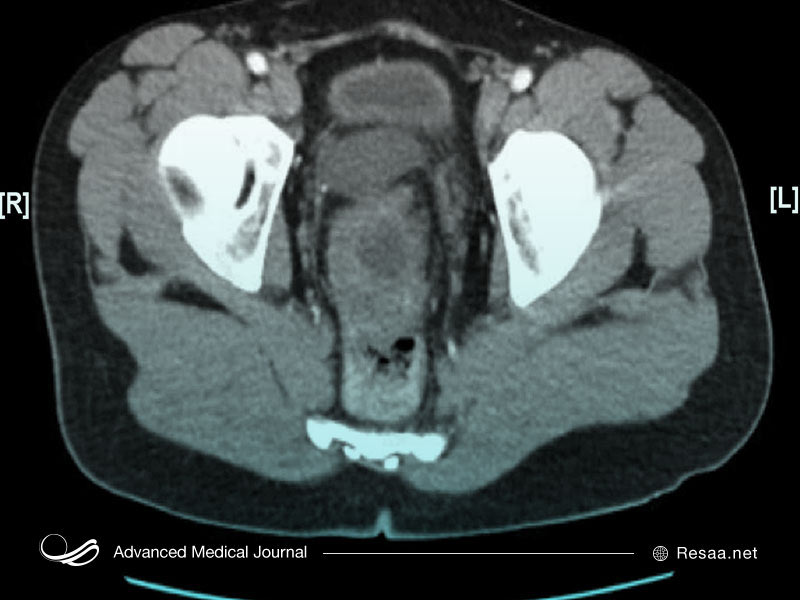

مثانه بخشی از سیستم ادراری است. این اندام، یک عضو تو خالی در لگن است که ادرار یا بول (یک مایع اضافی) را قبل از خروج از بدن ذخیره میکند.

مثانه بخشی از سیستم ادراری است. مثانه یک اندام تو خالی در لگن است که ادرار (بول) را قبل از خروج از بدن ذخیره میکند. دیواره مثانه انعطافپذیر است، بنابراین با پر شدن ادرار بزرگتر میشود (منبسط میشود) و با خالیتر شدن، کوچکتر میشود (منقبض میشود).

ادرار توسط کلیهها ساخته میشود و در امتداد 2 لوله بلند به نام حالب (میزنای یا مجرای ادراری) به مثانه سفر میکند. هنگامی که مثانه پر از ادرار است، عضلات موجود در دیواره مثانه سفت شده و ادرار را از طریق مجرای ادراری که از بدن خارج می شود، به بیرون هدایت میکند.

- چربی محیطی “perivesical” – لایه ای از چربی اطراف مثانه

- سرطان مثانه تهاجمی عضلانی در اعماق عضلات دیواره مثانه (muscularis propria) و گاهی در چربی اطراف مثانه رشد میکند.